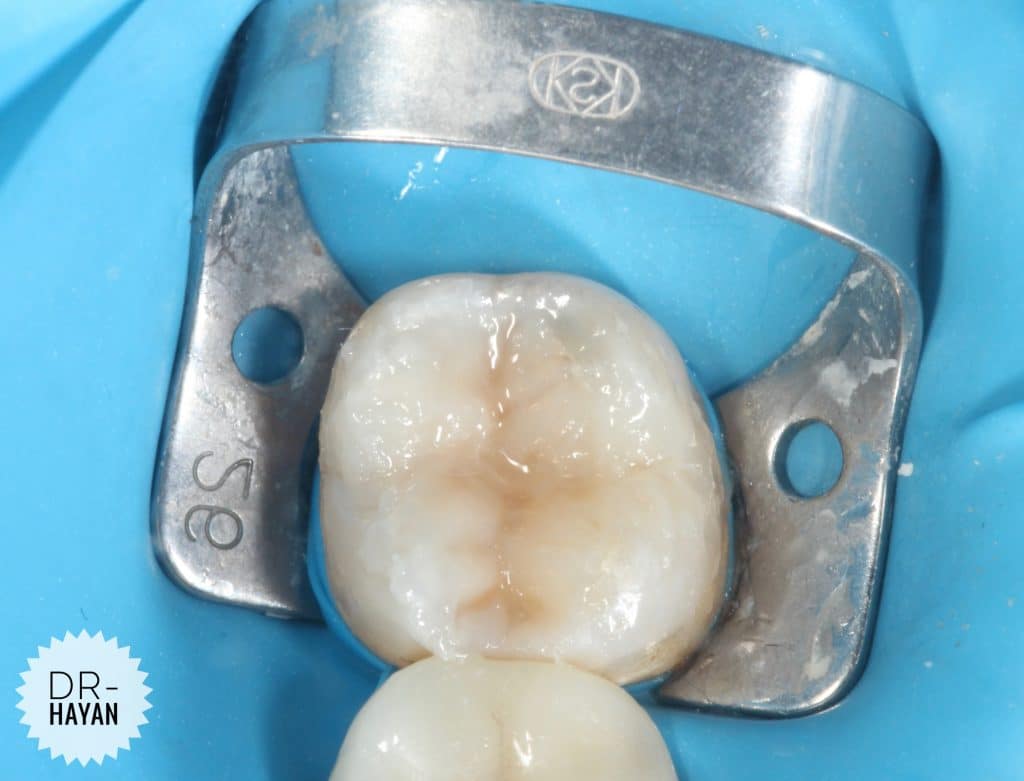

Initial view

lower 8 with Bad anatomy restoration & broken margin

With Sensitivity due to exposed dentin